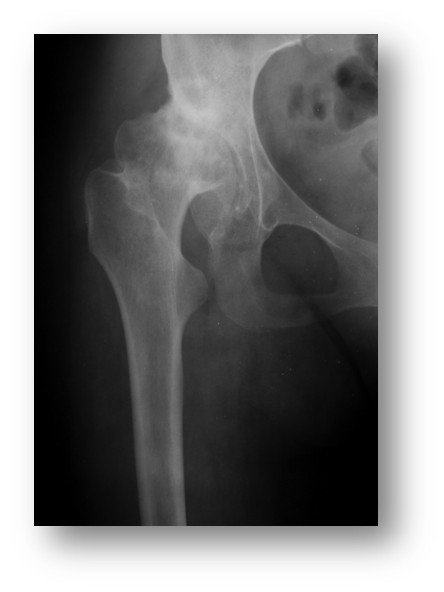

Przedstawiony radiogram wykazuje zmiany zwyrodnieniowe stawu biodrowego powstałe w wyniku:

Pytanie 72